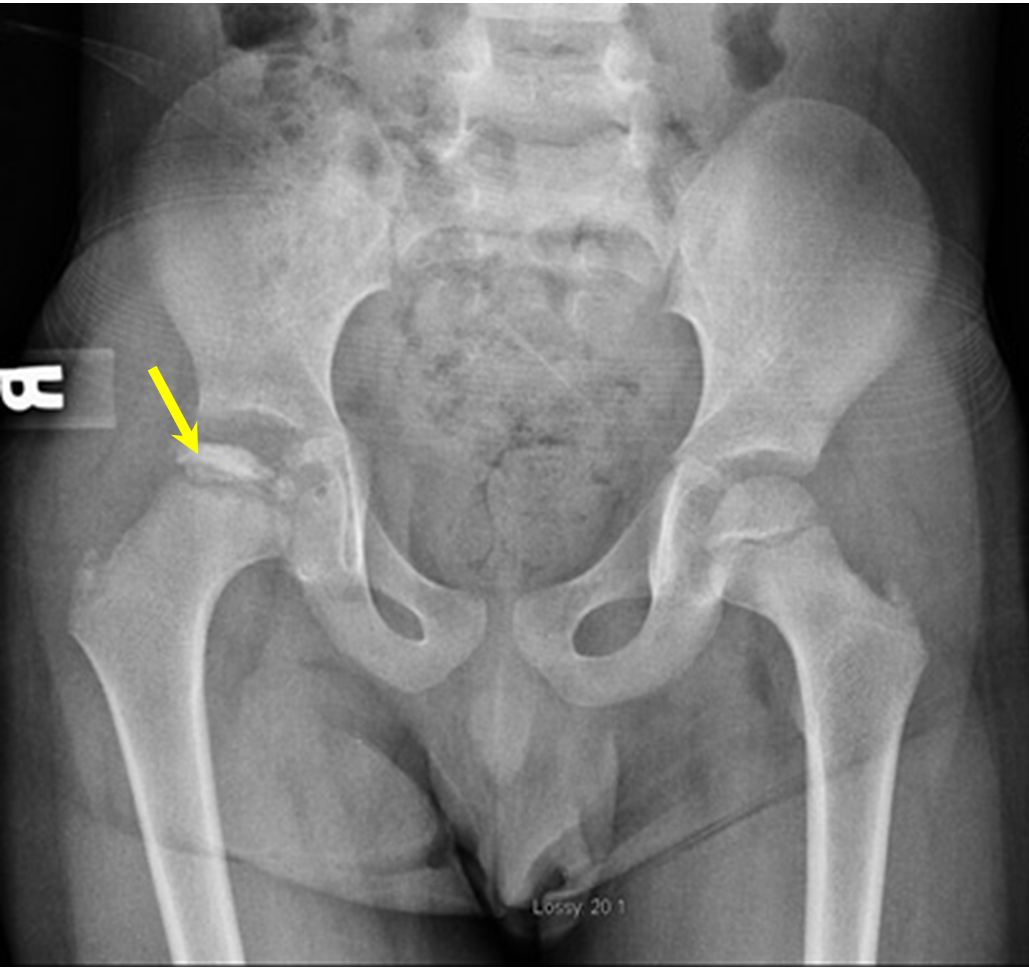

Question 2

Clinical question

A 66-year-old female presents with chronic lower back pain. An oblique lumbar spine X-ray is done and shown below. Based on the radiological findings, which of the following is the most likely diagnosis?

Options:

A) Spondylolysis

B) Spondylolisthesis

C) Crush vertebral fracture

D) Klippel Feil syndrome

Correct answer: A) Spondylolysis